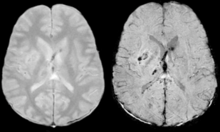

Gradient recalled echo (GRE) imaging is the conventional way to detect hemorrhage in CAA, however SWI is a much more sensitive technique that can reveal many micro-hemorrhages that are missed on GRE images.[6] A conventional gradient echo T2*-weighted image (left, TE=20 ms) shows some low-signal foci associated with CAA. On the other hand, an SWI image (center, with a resolution of 0.5 mm x 0.5 mm x 2.0 mm, projected over 8mm) shows many more associated low-signal foci. Phase images were used to enhance the effect of the local hemosiderin build-up. An example phase image (right) with yet higher resolution of 0.25 mm x 0.25 mm x 2.0 mm shows a clear ability to localize multiple CAA-associated foci.